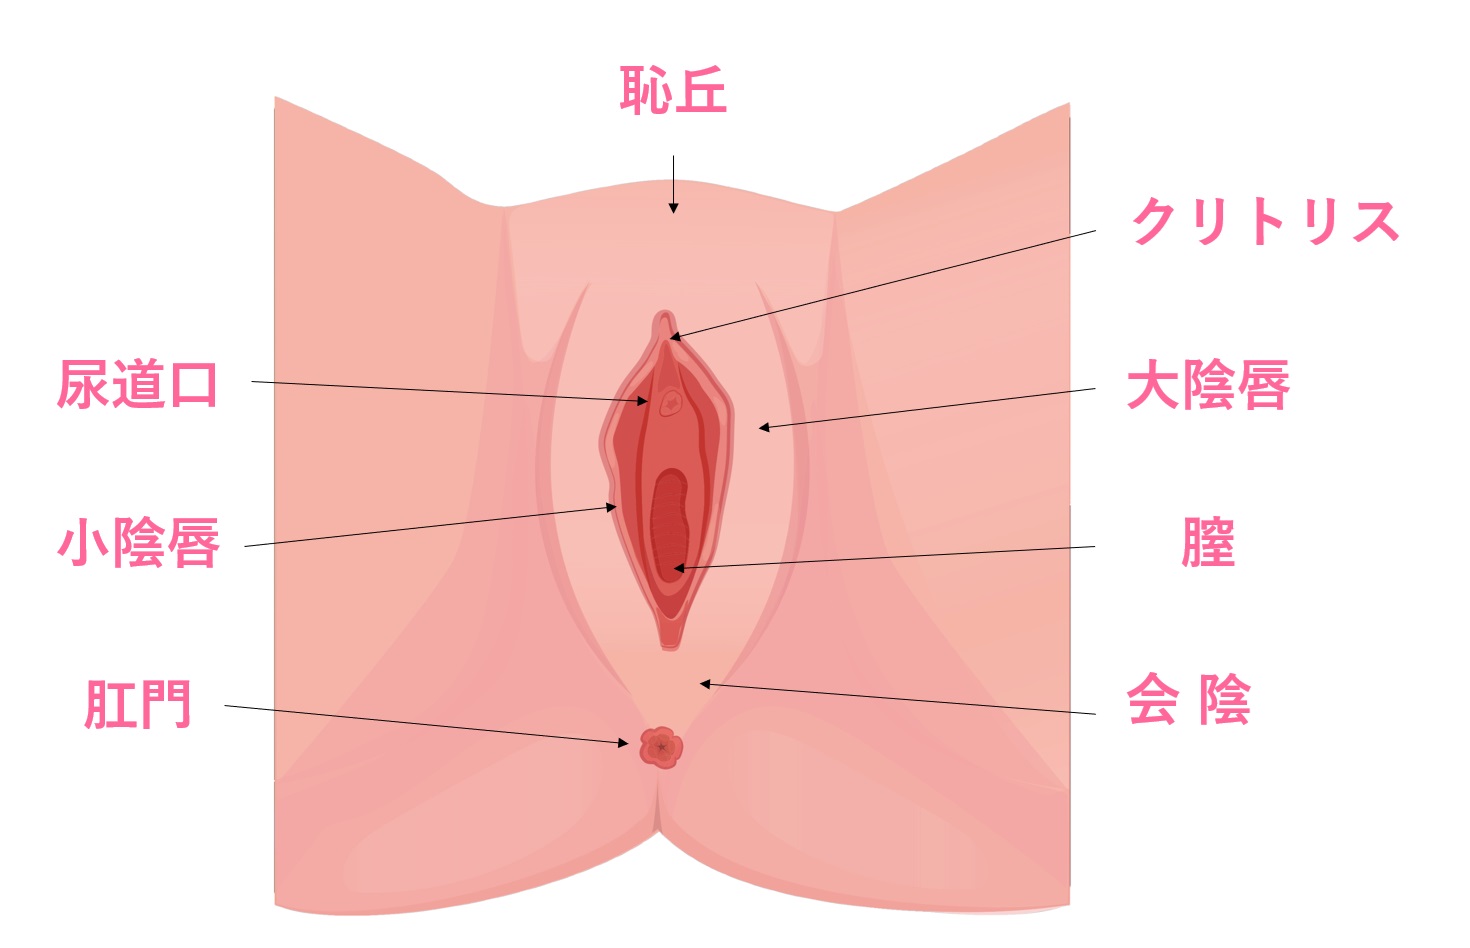

肉芽腫性外陰炎の1例臨床皮膚科 66巻2号医書.jp。

会陰部贅皮切除術銀座の美容外科・皮膚科ならルーチェクリニック。

会陰部、肛門のたるみの治療東京・銀座で産後、便秘による皮膚の傷跡、コンプレックスでお悩みならルクスクリニック。